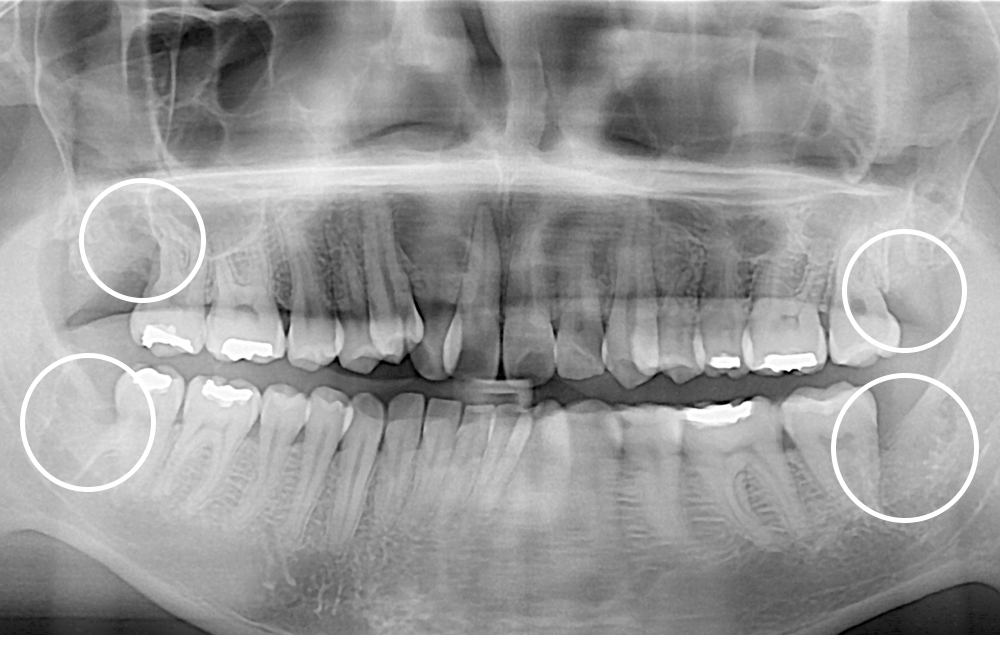

[사랑니] 매복 사랑니 발치

치료전 : 2020-04-08

세종치과는 구강악안면외과학 박사이신 원장님이 발치하는 치과입니다.